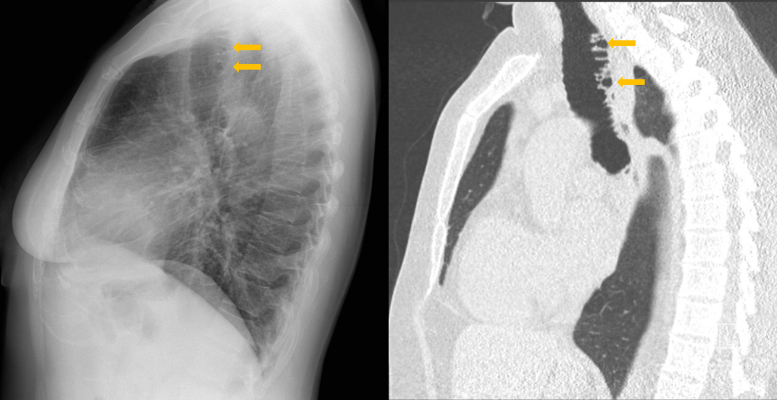

教学要点气管憩室病是一种罕见的良性疾病,其特征是单个或多个气管壁外袋,可以是先天性的,也可以是后天性的,通常在胸部高分辨率计算机断层扫描中偶然被诊断出来,一般情况下没有任何症状。

Teaching point: Tracheal diverticulosis is a rare and benign disorder, characterized by single or multiple tracheal wall outpouchings, either congenital or acquired, usually diagnosed incidentally on chest high‑resolution computed tomography, and in general remaining asymptomatic.